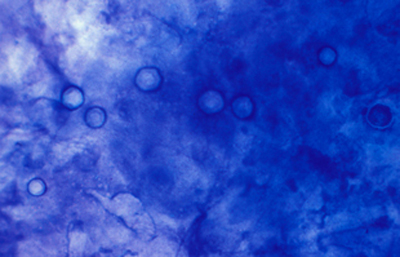

Blanco de Calcofluor

El uso del fluorocromo Blanco de Calcofluor no es excluyente de otras coloraciones, pues al ser en base acuosa no es permanente y la preparación puede lavarse en agua corriente para luego ser coloreadas con Giemsa, PAS u otras coloraciones, con el fin de reconfirmar los hallazgos microscópicos y volverlas permanentes para guardarlas.

Blanco de Calcofluor: Sobre el porta-objetos con el extendido ya fijado colocar unas gotas de Blanco de Calcofluor al 0.1% y de Azul de Evans 0.1%. Esperar 3 minutos. Cubrirlo con un cubre-objetos. Retirar con papel de filtro el exceso de líquido que se exterioriza por los bordes del cubre-objetos. Examen en el microscópio de fluorescencia. Emplear filtro excitador de 365 nm. y de emisión de 450-490 nm. Algunos autores favorecen emplear un filtro de emisión con longitud de onda más larga, fuera de la banda azul, en 520-550 nm. si bien con estas longitudes de onda la visualización de la emisión fluorescente es menos intensa.

Las imágenes de Acanthamoebas muestran una cápsula circular u ondulada, refringente de color azulado o verde manzana, notablemente más intensa que los materiales y tejidos que la rodean. Suelen medir de 12 a 16 µm de diámetro. El contenido del quiste es azul tenue. (Figura 37 , 38, 39 y 40)

Fig. 37 Blanco de Calcofluor (CW). Original x160

Fig. 38 CW, Original x250

Fig. 39 CW, Original x160

Fig. 40 CW, Original x160